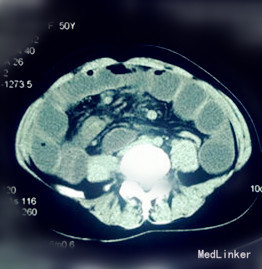

查体:生命体征平稳,体温37.5°C。未见黄疸;Murphy氏征(-);麦氏点无压痛、反跳痛;腹部明显膨隆,脐周压痛,肠鸣音活跃,可闻及气过水声。 辅查:腹部B超:胃及肠管扩张。 腹部立卧位片示:部分肠腔积气积粪伴小液平。 CT 示:肠扭转,回盲部异位并扩张。

诊断:腹痛查因:消化道穿孔? 治疗:入院后予禁食、胃肠减压、灌肠、抗感染、解痉、补液、支持等治疗,12 h 后病人腹痛无缓解,未排气排便,急诊查电子肠镜提示:横结肠近肝曲肠腔闭塞,肠镜无法通过。急诊在全麻下行剖腹探查术,术中探查见全小肠扭转并扩张,升结肠先天性游离并扩张,距屈氏韧带约10 cm 处小肠系膜根部有一裂隙,直径4 cm,升结肠穿过裂隙后致肠管被卡压扩张形成内疝,将小肠扭转复位并送回卡压升结肠,关闭小肠系膜裂隙。手术顺利,术后恢复良好出院。

先天性小肠系膜裂孔疝是一种罕见的疾病,是肠管通过先天性的小肠系膜裂孔而形成的腹内疝。本病临床表现为急性闭袢性肠梗阻,术前诊断非常困难。往往是术后,根据术中发现再结合术前的腹部CT 和动脉造影才找到诊断的依据。在CT 图像上,小肠系膜裂孔疝表现为扩张聚集的小肠袢,直接与前腹壁相邻,二者间无网膜覆盖,即在扩张的小肠壁和腹壁间没有脂肪组织存在。横结肠通常向下移位,有时可以将升结肠和降结肠向内侧推移移位。提醒各位临床医生,对一些不明原因且病情发展迅速的肠梗阻病人,应警惕有腹内疝的可能。